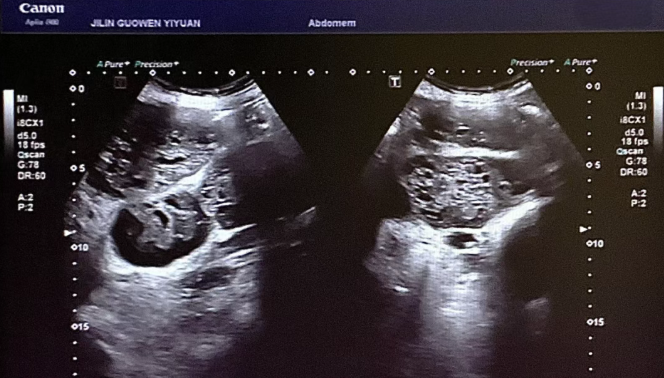

患者錢女士(化名),65 歲,因有高血壓病史而定期進(jìn)行體檢。在超聲檢查時(shí),醫(yī)生發(fā)現(xiàn)其腎臟存在占位性病變。超聲科團(tuán)隊(duì)借助高分辨率超聲成像技術(shù),清晰地觀察到腎臟內(nèi)的異?;芈晠^(qū),再結(jié)合血流信號(hào)分析,高度懷疑該病變可能為惡性腫瘤。為進(jìn)一步明確診斷,團(tuán)隊(duì)在超聲引導(dǎo)下進(jìn)行精準(zhǔn)穿刺,獲取病理組織。最終,病理報(bào)告確診該病變?yōu)?“小圓細(xì)胞惡性腫瘤”。

小圓細(xì)胞惡性腫瘤是一類較為少見的惡性疾病,常見于兒童及青少年,而發(fā)生在老年患者腎臟的情況則更為罕見。此類腫瘤具有很強(qiáng)的侵襲性,早期診斷對(duì)于治療方案的制定以及患者的預(yù)后都至關(guān)重要。錢女士雖然沒有出現(xiàn)典型癥狀,腹部查體也未觸及包塊,但得益于超聲科的細(xì)致檢查,病灶被及時(shí)發(fā)現(xiàn),這為后續(xù)的治療贏得了寶貴時(shí)間。